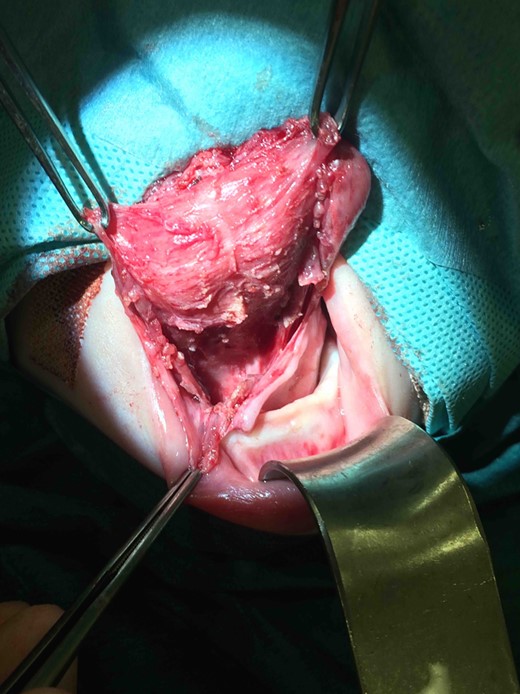

Intraoperative photograph demonstrating surgical excision of the thryoglossal duct cyst.

Clinic follow-up was expedited at age 5 weeks, as the cyst had increased rapidly in the preceding 10 days, resulting in impaired feeding. On examination, there was considerable swelling of the anterior tongue and floor of mouth, and the tongue was pushed superiorly against the hard palate and anteriorly, protruding past the lips. Interestingly there was no airway compromise. Fifteen millilitres of grey-brown fluid were aspirated from the cyst, which provided immediate reduction in swelling and improvement in feeding. It was planned to review the baby in 3 weeks with a view to future surgical excision, but to await microscopy and culture of the fluid and allow the neonate to grow further. Culture of the fluid showed no bacterial growth. However, at follow-up the cyst had re-collected to fill the entire oral cavity. Again there were no signs of airway compromise. Twenty millilitres of fluid were aspirated and the patient was booked for urgent surgical excision of the cyst. A horizontal sublingual incision above the submandibular duct openings was performed. The submandibular ducts and lingual nerves were identified and preserved. A cyst measuring 48 mm × 20 mm × 5 mm was excised, which extended up to the foramen caecum posteriorly (Figs 2–4). The defect was closed with vicryl rapide 4/0, and a small opening was left anteriorly and posteriorly to facillitate drainage. Histology showed that the cyst wall was lined by stratified squamous epithelium in some areas and bundles of smooth muscle in others. Additionally, there were small cystic structures lined by mucin-producing columnar cells. These appearances were consistent with the clinical diagnosis of a cystic thyroglossal duct remnant.